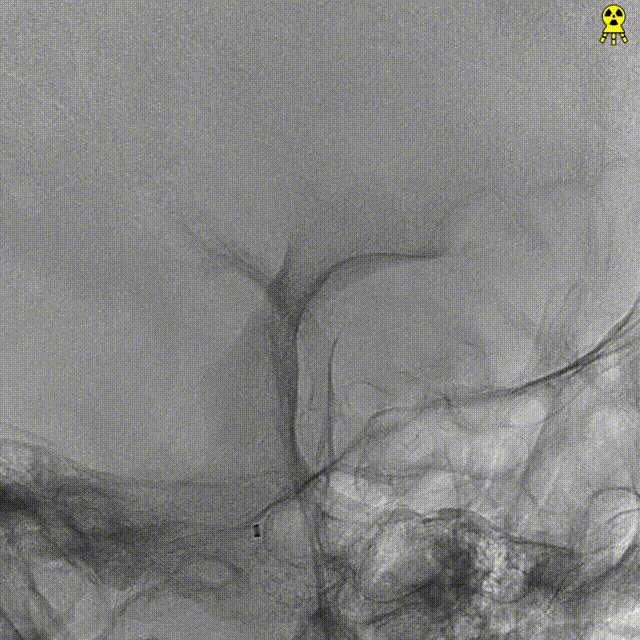

DSA:提示左侧大脑前动脉A2段动脉瘤,其他血管造影未见明显异常。

远端通路导管到位:

微导管到位:Synchro微导丝导引支架微导管通过病变血管进入。

支架到位,远端打开(工作位):支架释放过程中,轻柔推送支架系统,支架释放,打开良好。

术后造影:支架覆盖夹层动脉瘤,贴壁良好。

术后造影:

强易达(Choydar)血流导向密网支架术中操作顺利,支架推送及释放过程平顺,未见管壁损伤,支架喇叭口形状设计贴壁效果好;径向支撑力高。